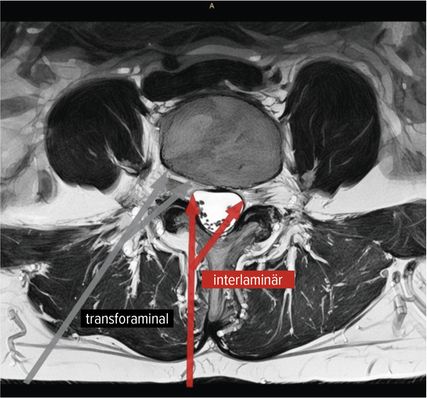

Der interlaminäre endoskopische Zugang bietet Vorteile in den Segmenten L4/5 und L5/S1 aufgrund der Weite des Interlaminärfensters. Dem Chirurgen kommen dabei die Erfahrungen des offenen interlaminären Zugangs zugute, da die Ausrichtung des Sichtfeldes und anatomische Orientierung ident sind. Während der transforaminäre Zugang vorwiegend bei Diskektomien zum Einsatz kommt, hat die Entwicklung des IL-Zugangs das Indikationsspektrum erweitert. Zentrale Spinalkanalstenosen, Rezessusstenosen, aber auch die kontralaterale Foraminotomie sind mögliche Einsatzgebiete.11–13 Abbildung 2 illustriert die interlaminäre (roter Pfeil) und transforaminäre (grauer Pfeil) endoskopische lumbale Zugangstrajektorien (MRI-t2-gewichtet). Abbildung 3 zeigt das Kambin-Dreieck. Dieses weist die Form eines rechtwinkligen Dreiecks auf und wird durch die austretende Nervenwurzel (Hypotenuse), den Duralsack, den Processus articularis superior des Facettengelenkes und die Grundplatte (Basis) begrenzt. Es stellt eine sichere Landungszone für das Endoskop im Neuroforamen dar.